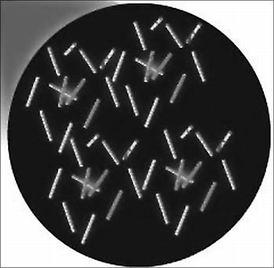

⑤通過活體組織學檢查可見到肉芽腫,抗酸染色可發現抗酸桿菌 (acid-fast bacillus)。